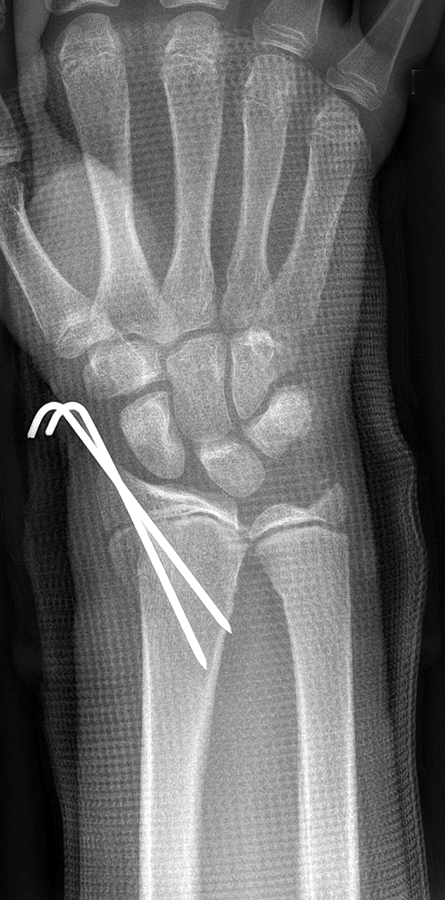

The implantation of plates and screws in the distal radius is appropriate for unstable, intraarticular, compound, and/or comminuted fractures and allows stable fixation compatible with early mobilization on only protective removable splinting. Drawbacks of such internal fixation, however, is the necessity of additional soft-tissue injury for the exposure during implantation; thereafter, the potential to irritate tendons near the components, causing tendinopathy and possible tendon rupture. Currently, the most common complications directly related to distal radius plate fixation include tenosynovitis, tendon attrition, and rupture often necessitating hardware removal. The most obvious obstacle when adopting CRPP besides the limited stability of the construct and the necessity of lengthy immobilization is the extension of pins outside of the bone which can cause an increased risk of infection (Fig 2).

After closed reduction a dorsal re-dislocation of 25° occurred (Fig 4a). There are additional apparent signs of instability: dorsal comminution (Fig 4a) and fracture of the ulnar styloid (Fig 4b). Therefore, a considerable potential for further dislocation is present which is likely to occur in a cast. This young, active, and demanding patient wishes to return to her activities as early as possible. This can only be achieved with an operative fracture fixation. The nail was chosen instead of a plate. This allowed an almost instant functional use of her hand, which allowed her to return to work at 2 weeks postoperatively without additional fixation or a splint and full unprotected function of her wrist at 6 weeks.